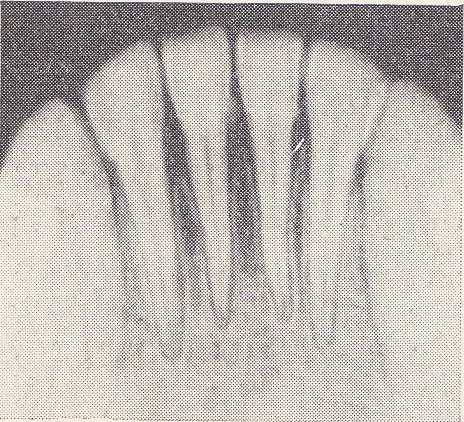

| Рис. 7. Деструкция твердых пластинок межзубных перегородок в области 31, 32, 41, 42 зубов, остеопороз. Высота перегородок находится на уровне эмалево-цементной границы. На смежных поверхностях коронок 31 и 32 зубов выступающие проекции зубного камня. Рис. 8. Область 31, 32, 41, 42 зубов. Высота межзубных перегородок на уровне эмалево-цементной границы, вершины их нечеткие. Периодонтальная щель у шеек 31 и 41 зубов расширена. |